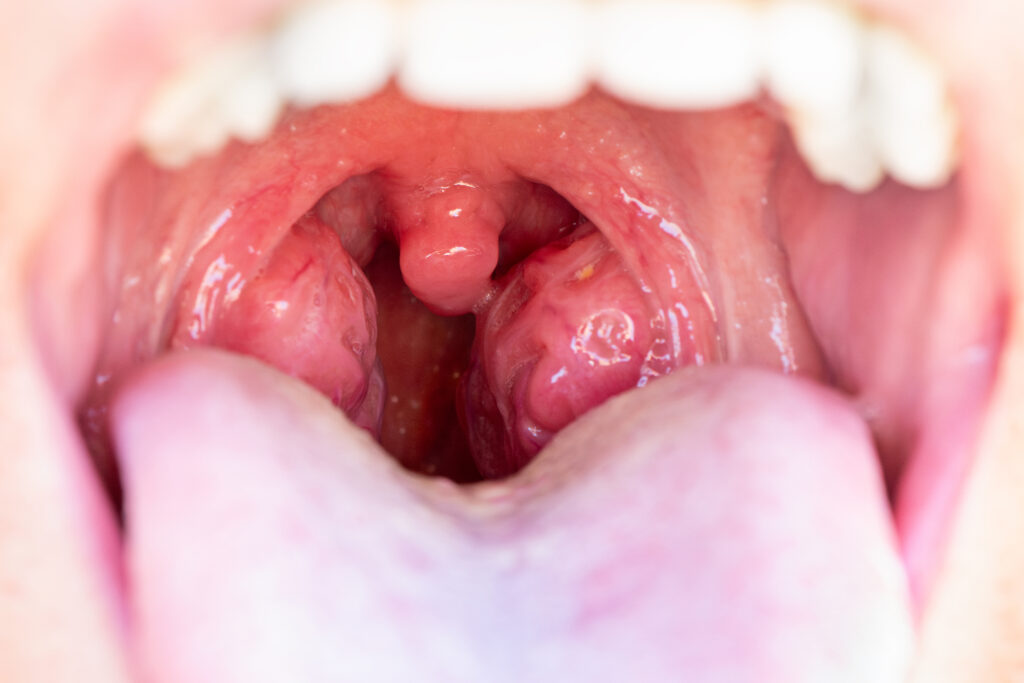

Tonsillitis is the inflammation or infection of the tonsils – the two soft, oval-shaped tissues at the back of your throat. These little glands are part of your immune system and act as a first line of defense against germs. But when viruses or bacteria overwhelm them, they swell up, get painful, and make swallowing difficult.While people often call it a sore throat, true tonsillitis comes with other signs like swollen tonsils, fever and sometimes visible white patches at the back of your throat.

• Red, swollen tonsils

• White or yellow patches on the tonsils